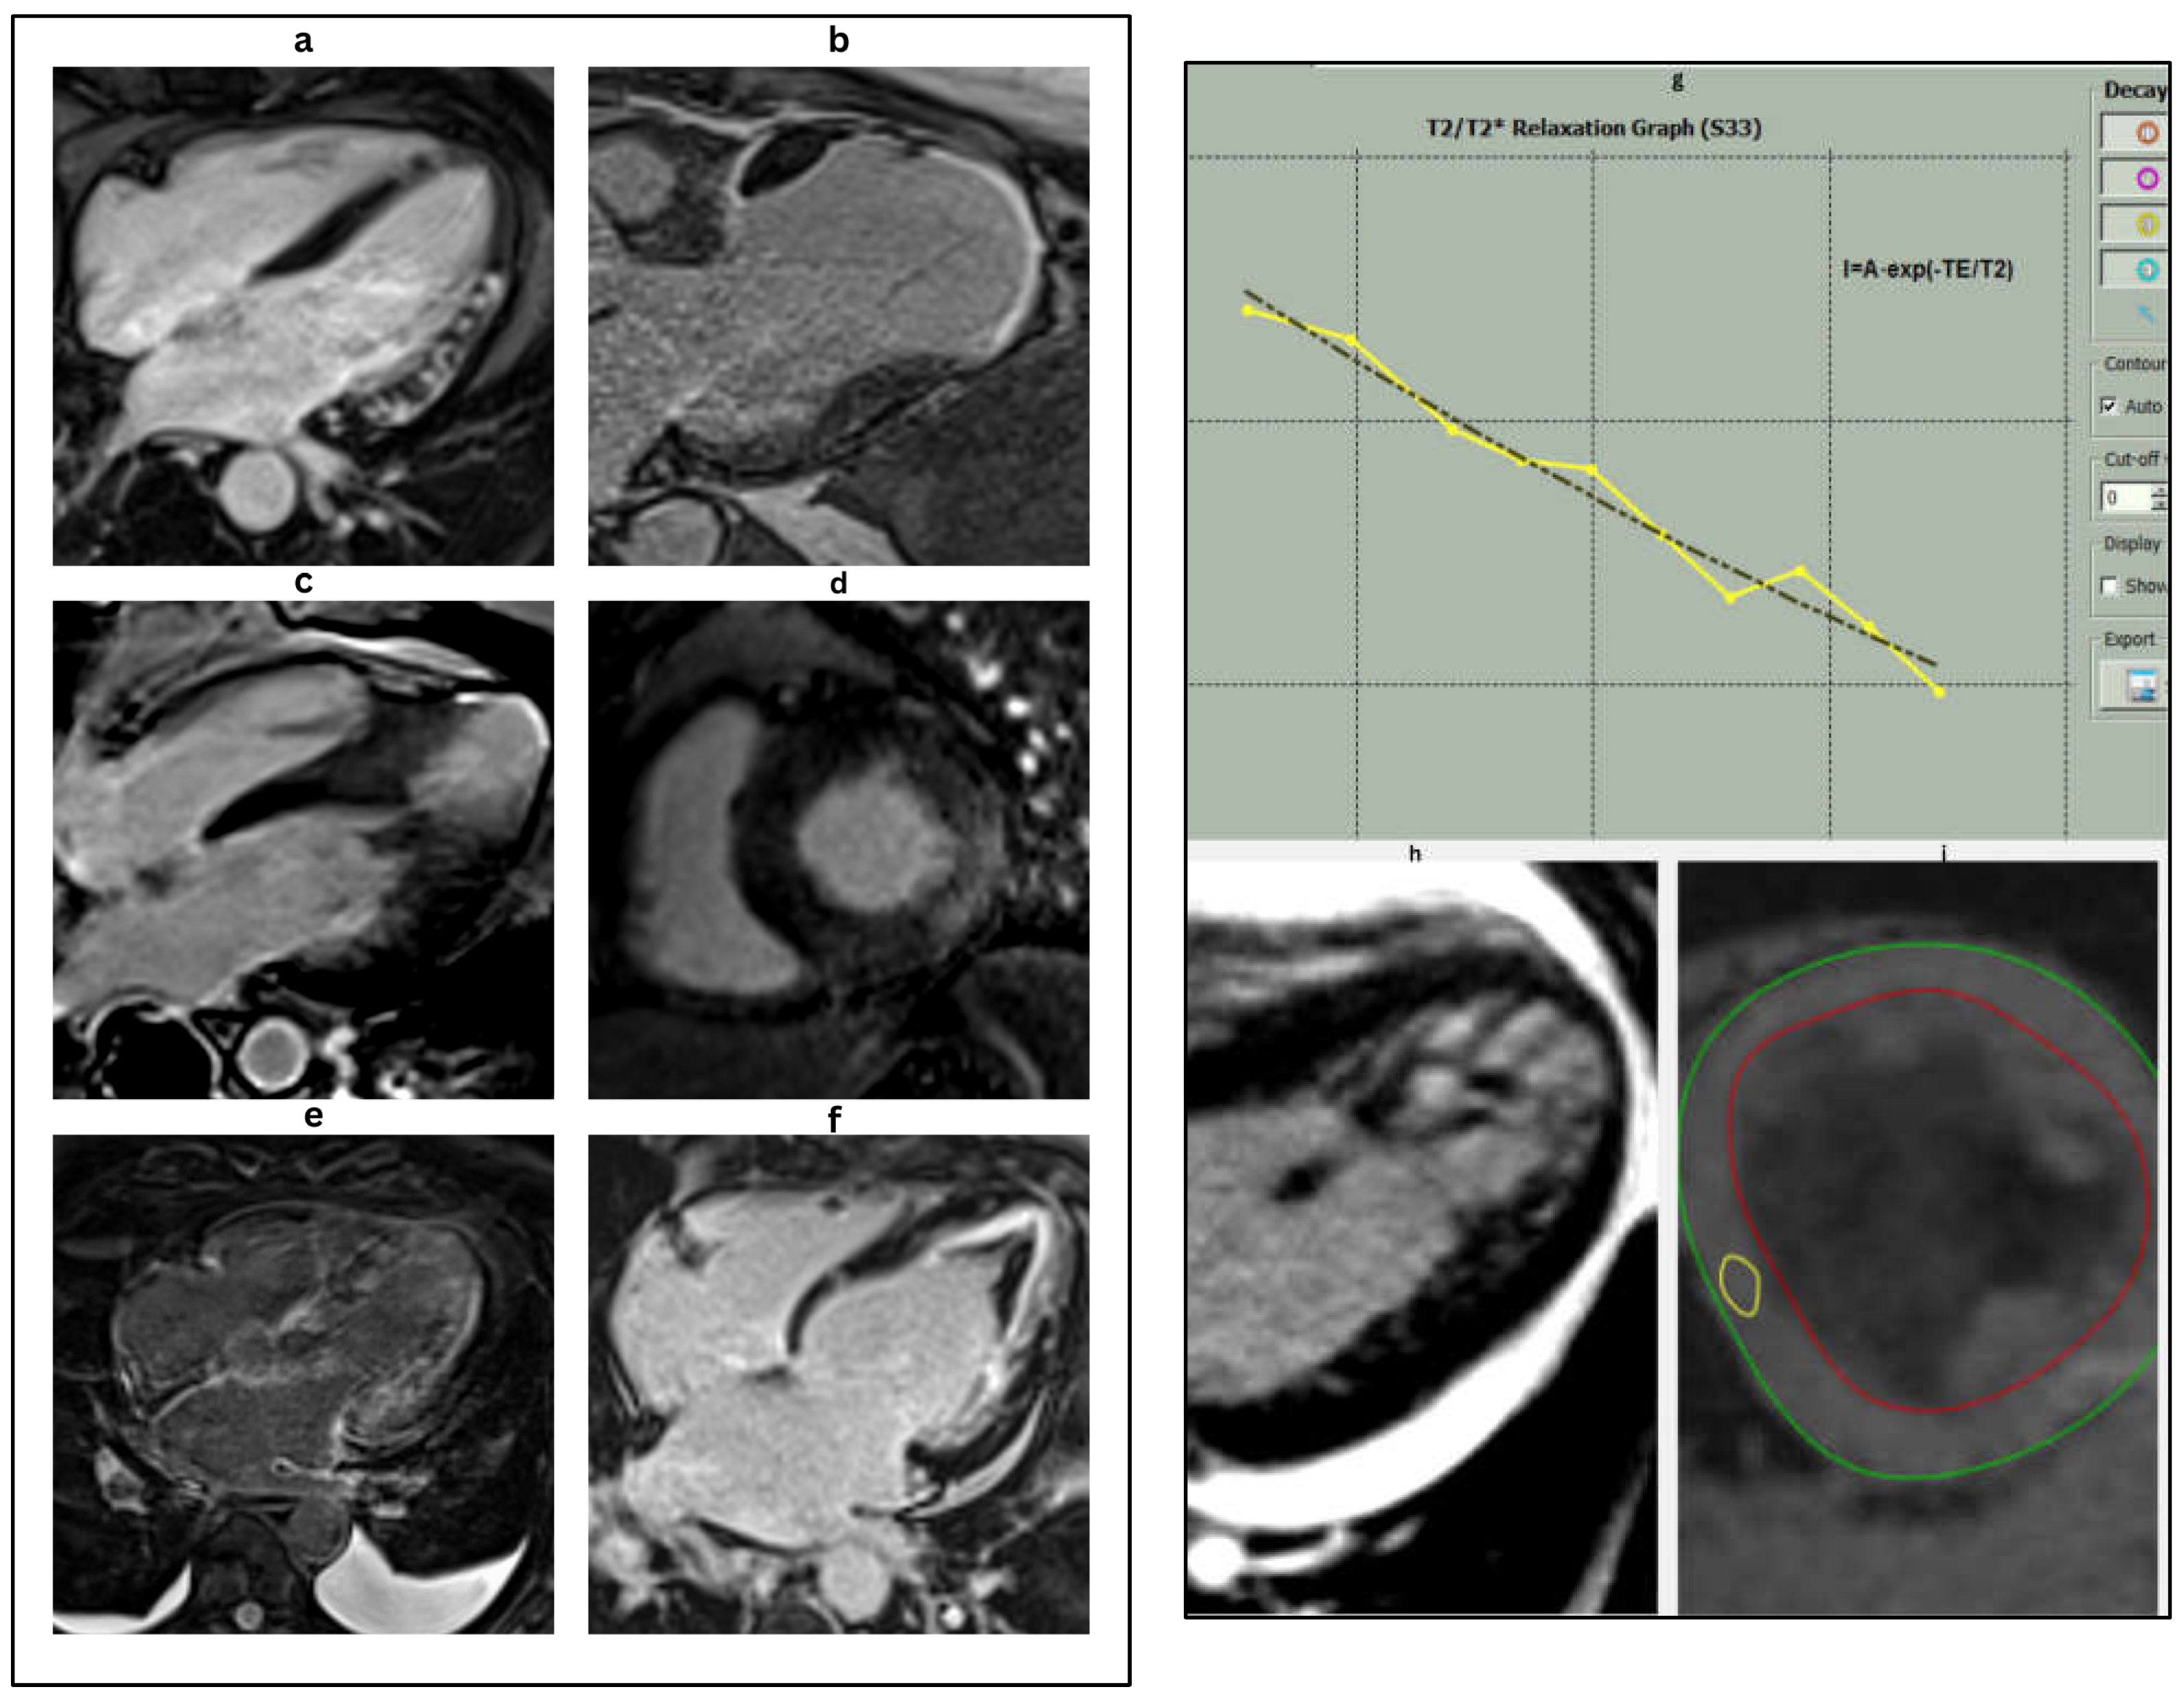

Table 11. Characteristic cardiac MRI findings in heart failure etiologies (Figure 6 and Figure 7) [55,56,57,58,59].

ConditionLate Gadolinium Enhancement (LGE)T1 Mapping/ECVOther Key CMR Features

Ischemic CardiomyopathySubendocardial or transmural in coronary artery distribution↑ native T1 and ECV in infarcted zonesWall thinning, scar extent correlates with prognosis

Dilated CardiomyopathyMid-wall septal or diffuse patchyMild ↑ T1 and ECVChamber dilation, reduced EF, global hypokinesia

Hypertrophic CardiomyopathyFocal patchy LGE at RV insertion points or mid-wall↑ native T1 and ECV (variable)Asymmetric hypertrophy, LVOT obstruction, apical variant

Cardiac AmyloidosisGlobal subendocardial or transmural; difficulty nulling myocardiumMarkedly ↑ native T1 and ECVBiatrial enlargement, thickened valves/pericardium, small LV

Anderson-Fabry DiseaseFocal inferolateral wall LGE↓ native T1Concentric hypertrophy, no ECV increase

MyocarditisSubepicardial or mid-wall (especially lateral wall)↑ native T1 and T2Edema on T2, positive Lake Louise criteria

SarcoidosisPatchy, multifocal LGE (basal septum ‘hook sign’ often seen↑ native T1 and ECVRV involvement, wall thinning, edema possible

Iron Overload (Hemochromatosis)Usually none unless fibrosis is advanced↓ native T1Reduced T2* signal (<20 ms diagnostic), biventricular dilation

Arrhythmogenic RV Cardiomyopathy (ARVC)RV free wall LGE (if visible)VariableRV dilation, akinesia, fatty infiltration (on black-blood imaging)

Figure 6. Characteristic cardiac MRI findings in different HF etiologies. (a): Four chamber delayed enhancement CMR in a patient with myocarditis. Late gadolinium enhancement (LGE) is seen in the mid-myocardial to subepicardial layers of the anterolateral wall, a typical non-ischemic pattern of injury. These findings are consistent with inflammatory myocardial involvement, commonly seen in viral or immune-mediated myocarditis. (b): Cardiac magnetic resonance (CMR) image demonstrating ischemic cardiomyopathy. The image reveals marked apical thinning with transmural late gadolinium enhancement (LGE) in the left anterior descending (LAD) artery territory, consistent with chronic infarction and scar formation. These findings are typical of prior anterior myocardial infarction with associated adverse remodeling. (c): 4-ch delayed enhancement CMR in apical HCM showing mid-septal LV hypertrophy and apical scar. (d): Short-axis LGE image revealing inferolateral mid-myocardial to epicardial lateral wall hyper-enhancement and concentric LV hypertrophy in Fabry’s disease. (e): Cardiac magnetic resonance imaging (CMR) in the 4-chamber view with late gadolinium enhancement (LGE) in a patient with cardiac amyloidosis. The image demonstrates diffuse, global subendocardial, and transmural late gadolinium enhancement, a hallmark feature of cardiac amyloid infiltration. Note the difficulty in nulling the myocardial signal, another characteristic finding in cardiac amyloidosis. (f): Cardiac magnetic resonance (CMR) image in a patient with endomyocardial fibrosis (EMF). The four-chamber late gadolinium enhancement (LGE) image demonstrates apical scarring with superimposed thrombus in the left ventricle, characteristic of EMF, and reflects chronic fibrotic remodeling leading to restrictive physiology. (g): T2* relaxation curve showing exponential signal decay over time, characteristic of myocardial iron overload. The yellow line represents the T2 relaxation process, which describes the decay of transverse magnetization due to interactions between nearby spins. The black line shows the T1 relaxation process, which depicts the recovery of longitudinal magnetization as spins realign with the external magnetic field. These curves are fundamental for differentiating tissue types in MRI based on their distinct relaxation times. The rapid drop in signal intensity reflects shortened T2* values due to increased magnetic susceptibility from iron deposition. Quantitative T2* analysis is essential for assessing the severity of cardiac siderosis, particularly in conditions such as thalassemia major or hemochromatosis. (h): LV cine image displaying prominent trabeculations and deep intertrabecular recesses, predominantly in the apical and lateral segments characteristic of left ventricular non-compaction (LVNC). (i): Short-axis cardiac magnetic resonance (CMR) image of the mid-left ventricle used for T2* mapping. The green line represents the outer boundary of the myocardial wall, while the red line indicates the inner endocardial lining. The region of interest (ROI) (in yellow) is typically placed in the interventricular septum to quantify myocardial T2* relaxation times. This technique is essential for detecting and monitoring myocardial iron overload, with lower T2* values indicating increased iron deposition.